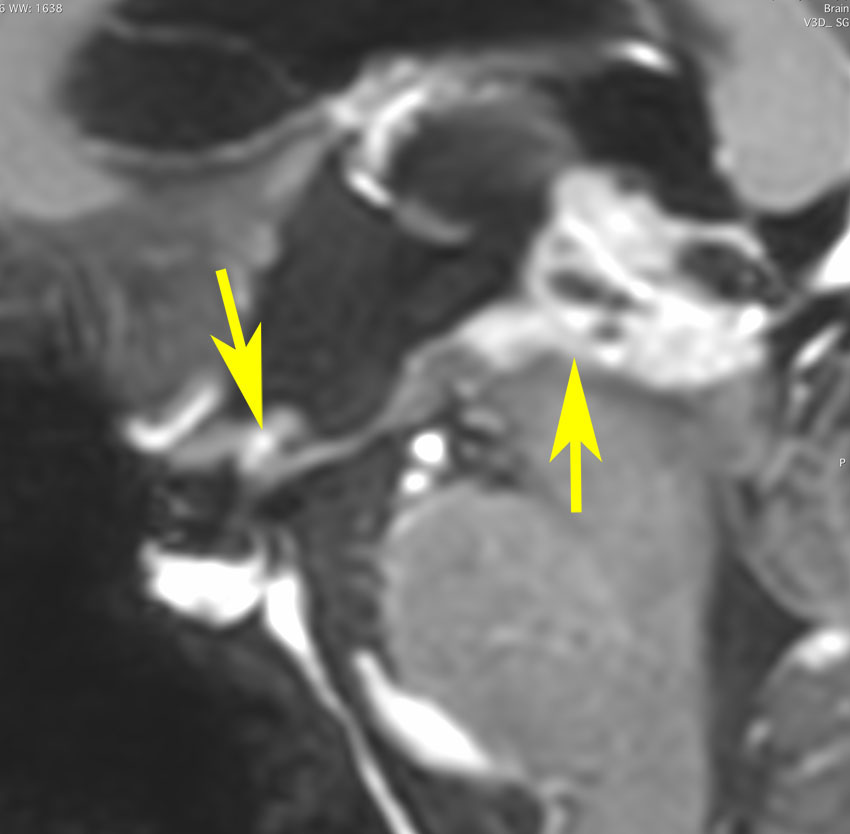

germinomaの視床浸潤:ミッキーマウスの耳

松果体ジャーミノーマは両側視床に浸潤して視床浮腫を生じます。真ん中に第3脳室後半部の割れ目が残っているのが特徴的な所見です。ミッキーマウスの耳みたいになります。かなり特異的な所見であり診断に有用です。右下は治療後です。